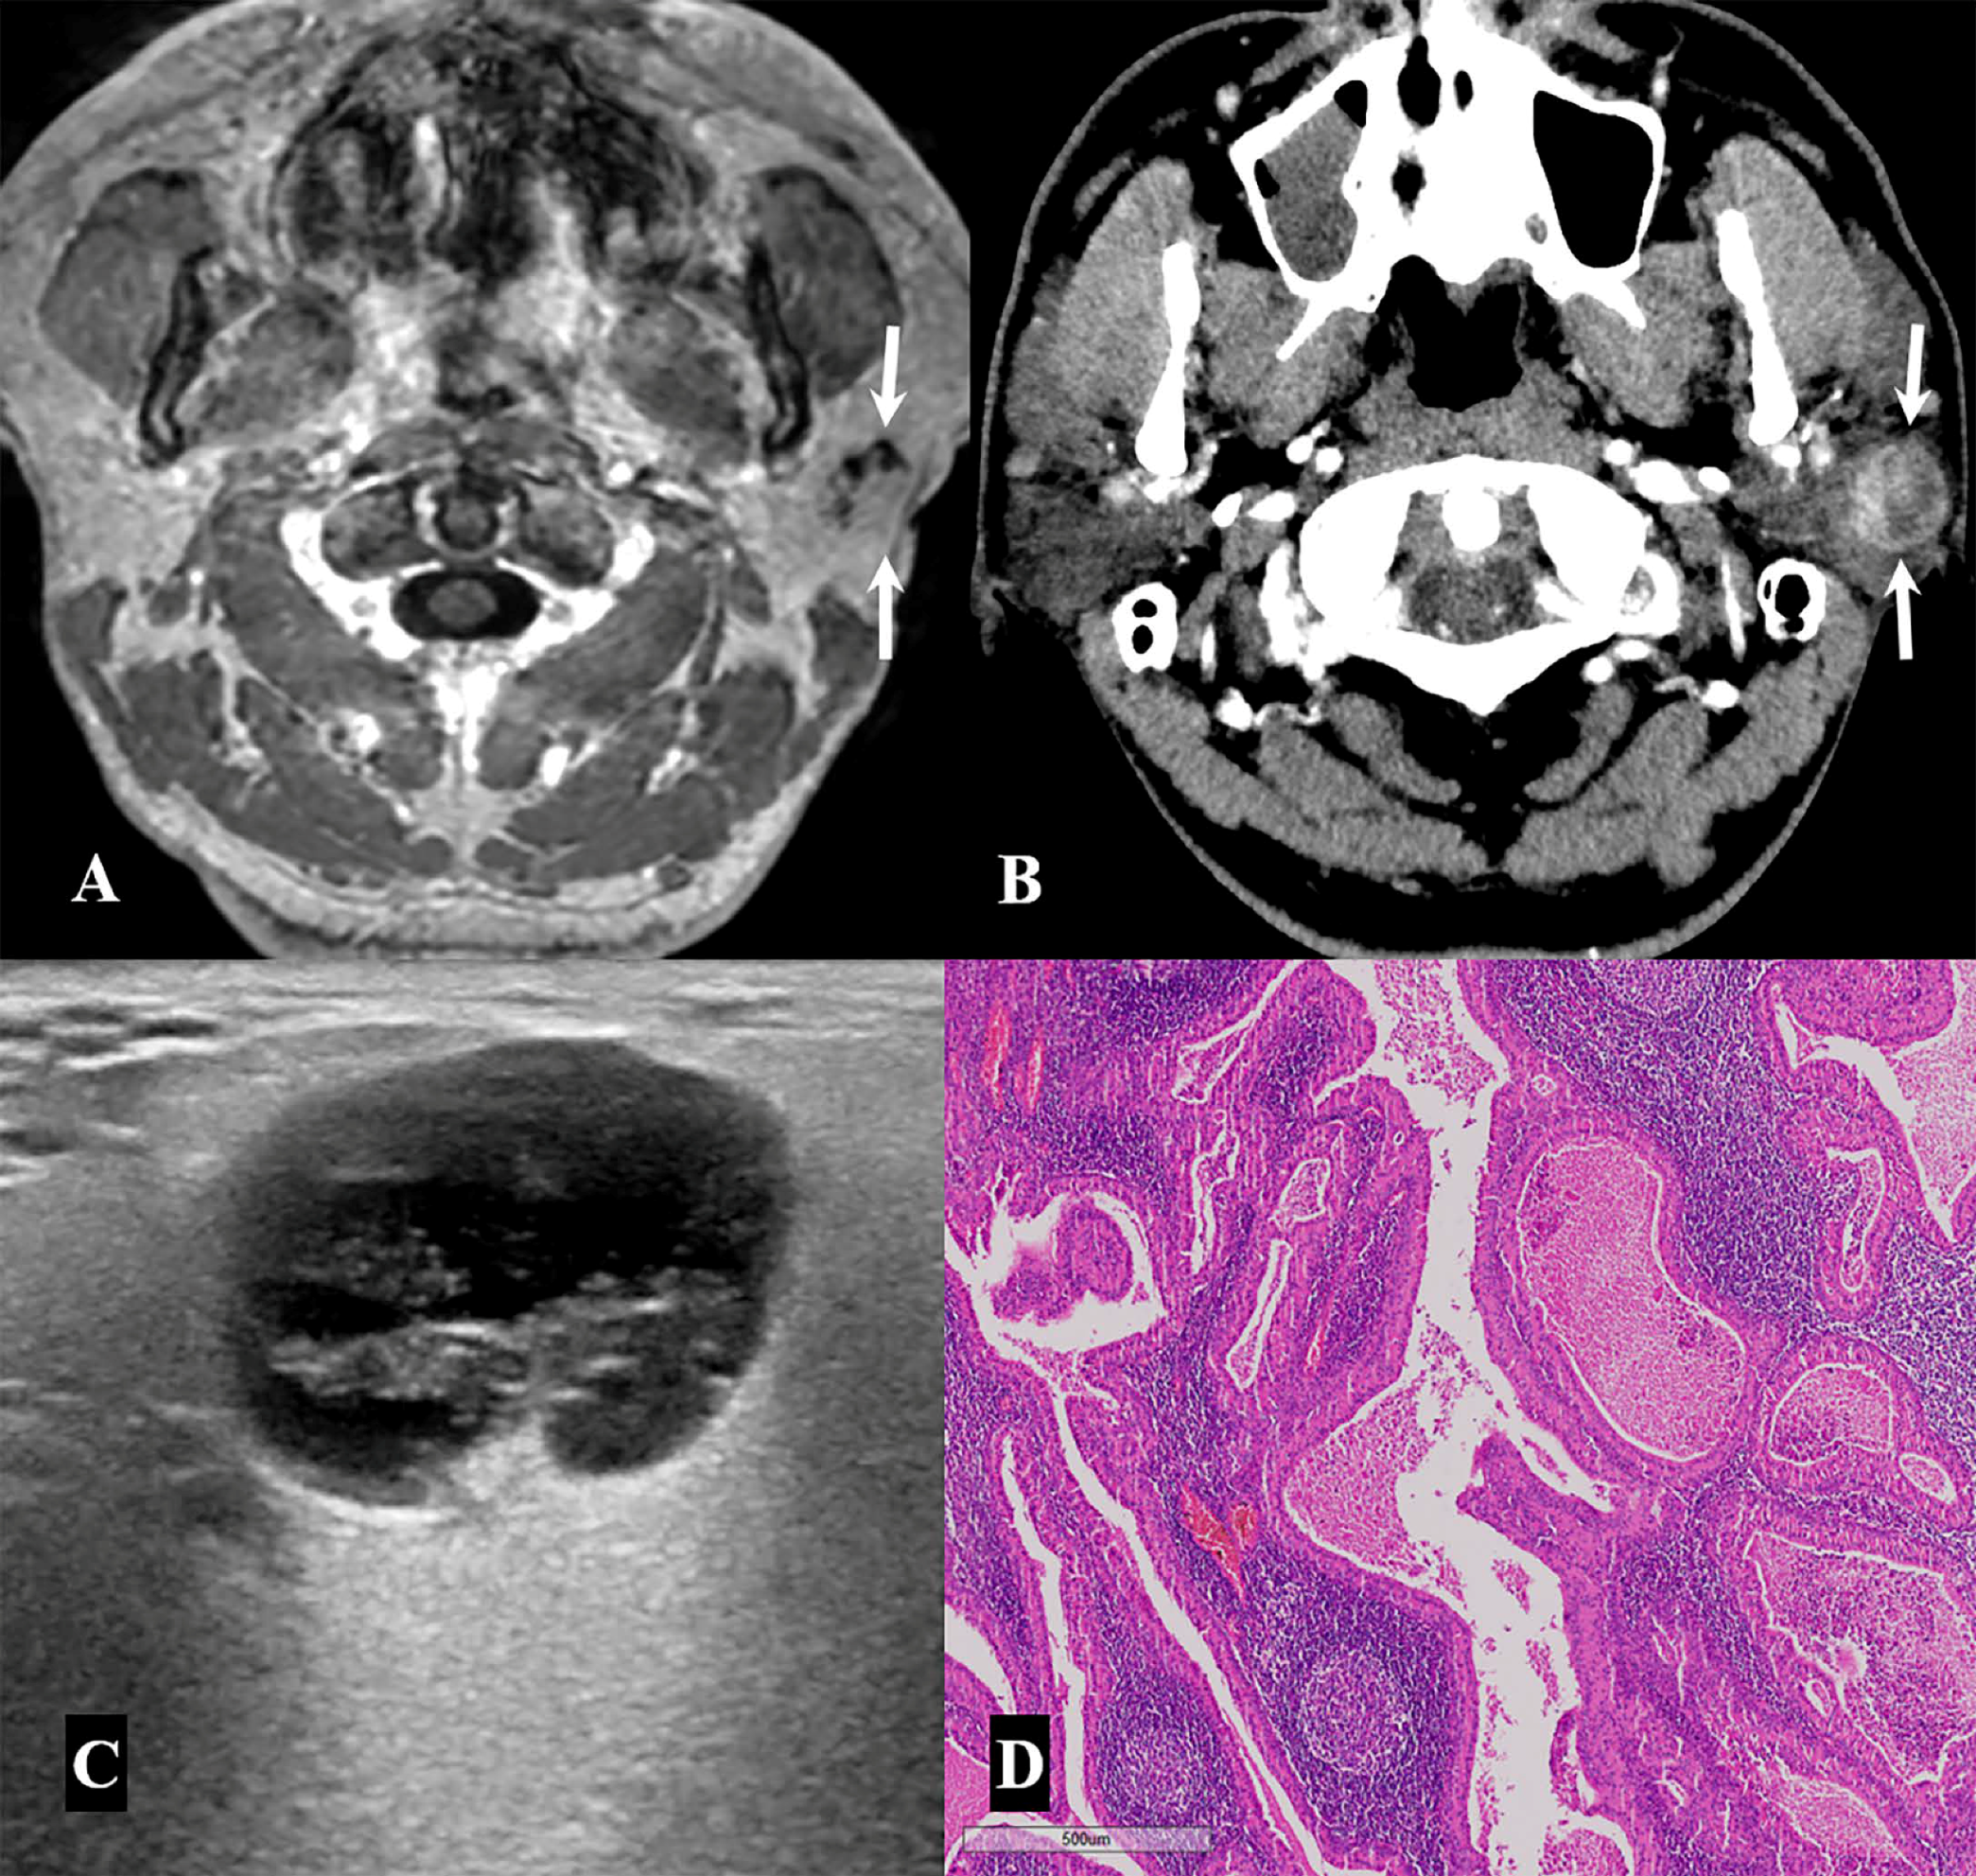

| Warthin tumor | 18/49 (36.7%) |